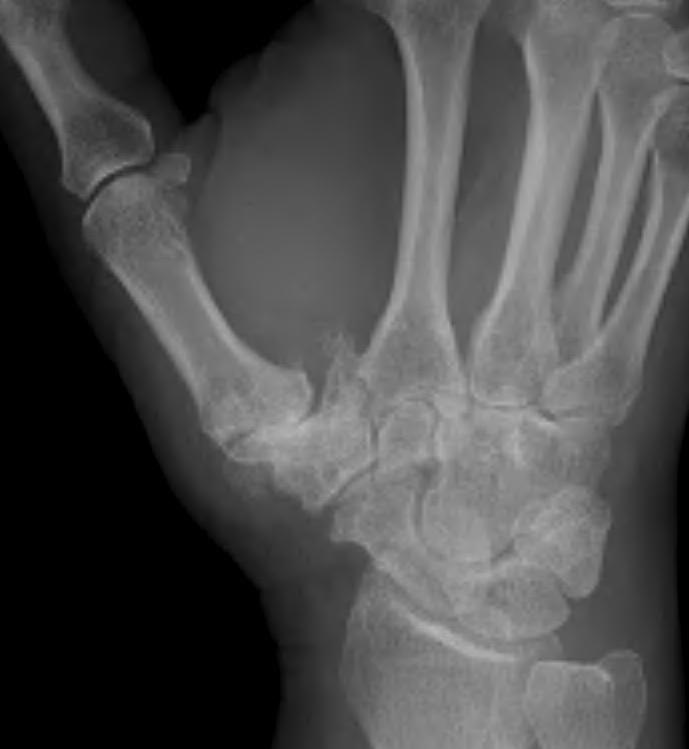

Eaton Classification

| Stage I | Stage II | Stage III | Stage IV |

|---|---|---|---|

|

Xray normal Synovitis |

Joint space narrowed Mild subluxation |

Severe joint space OA Radial subluxation of joint |

CMC + STT OA |

![]() |